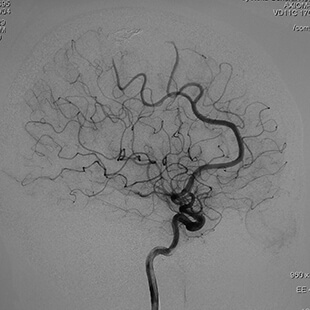

Neurosurgery10 脳動静脈奇形治療のこれまでとこれから 新到着 新NS 10】脳動静脈奇形治療のこれまでとこれから NOWの詳細情報

新到着 新NS 10】脳動静脈奇形治療のこれまでとこれから NOW。脳神経外科 専門治療 脳動静脈奇形|東京慈恵会医科大学附属柏病院。脳・脊髄動静脈奇形と頭蓋内・脊髄硬膜動静脈瘻。2017年発行の第1版です。【JMECC受講テキスト】内科救急診療指針2022【裁断済み】。脳神経領域:320列面検出器CTの最新画像がもたらす新たな展開。よろしくお願い致します。